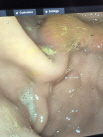

Ein flexibles Endoskop wird in die Nüstern des stehenden Pferdes eingeführt, bis zum Kehlkopf vorgeschoben und dann vom Pferd abgeschluckt. Über die Speiseröhre gelangt man in den Magen. Mithilfe von Luft wird der Magen aufgeweitet, sodass die Magenschleimhaut gut betrachtet und abgebildet werden kann. Außerdem kann man von auffälligen Lokalisationen Proben entnehmen.